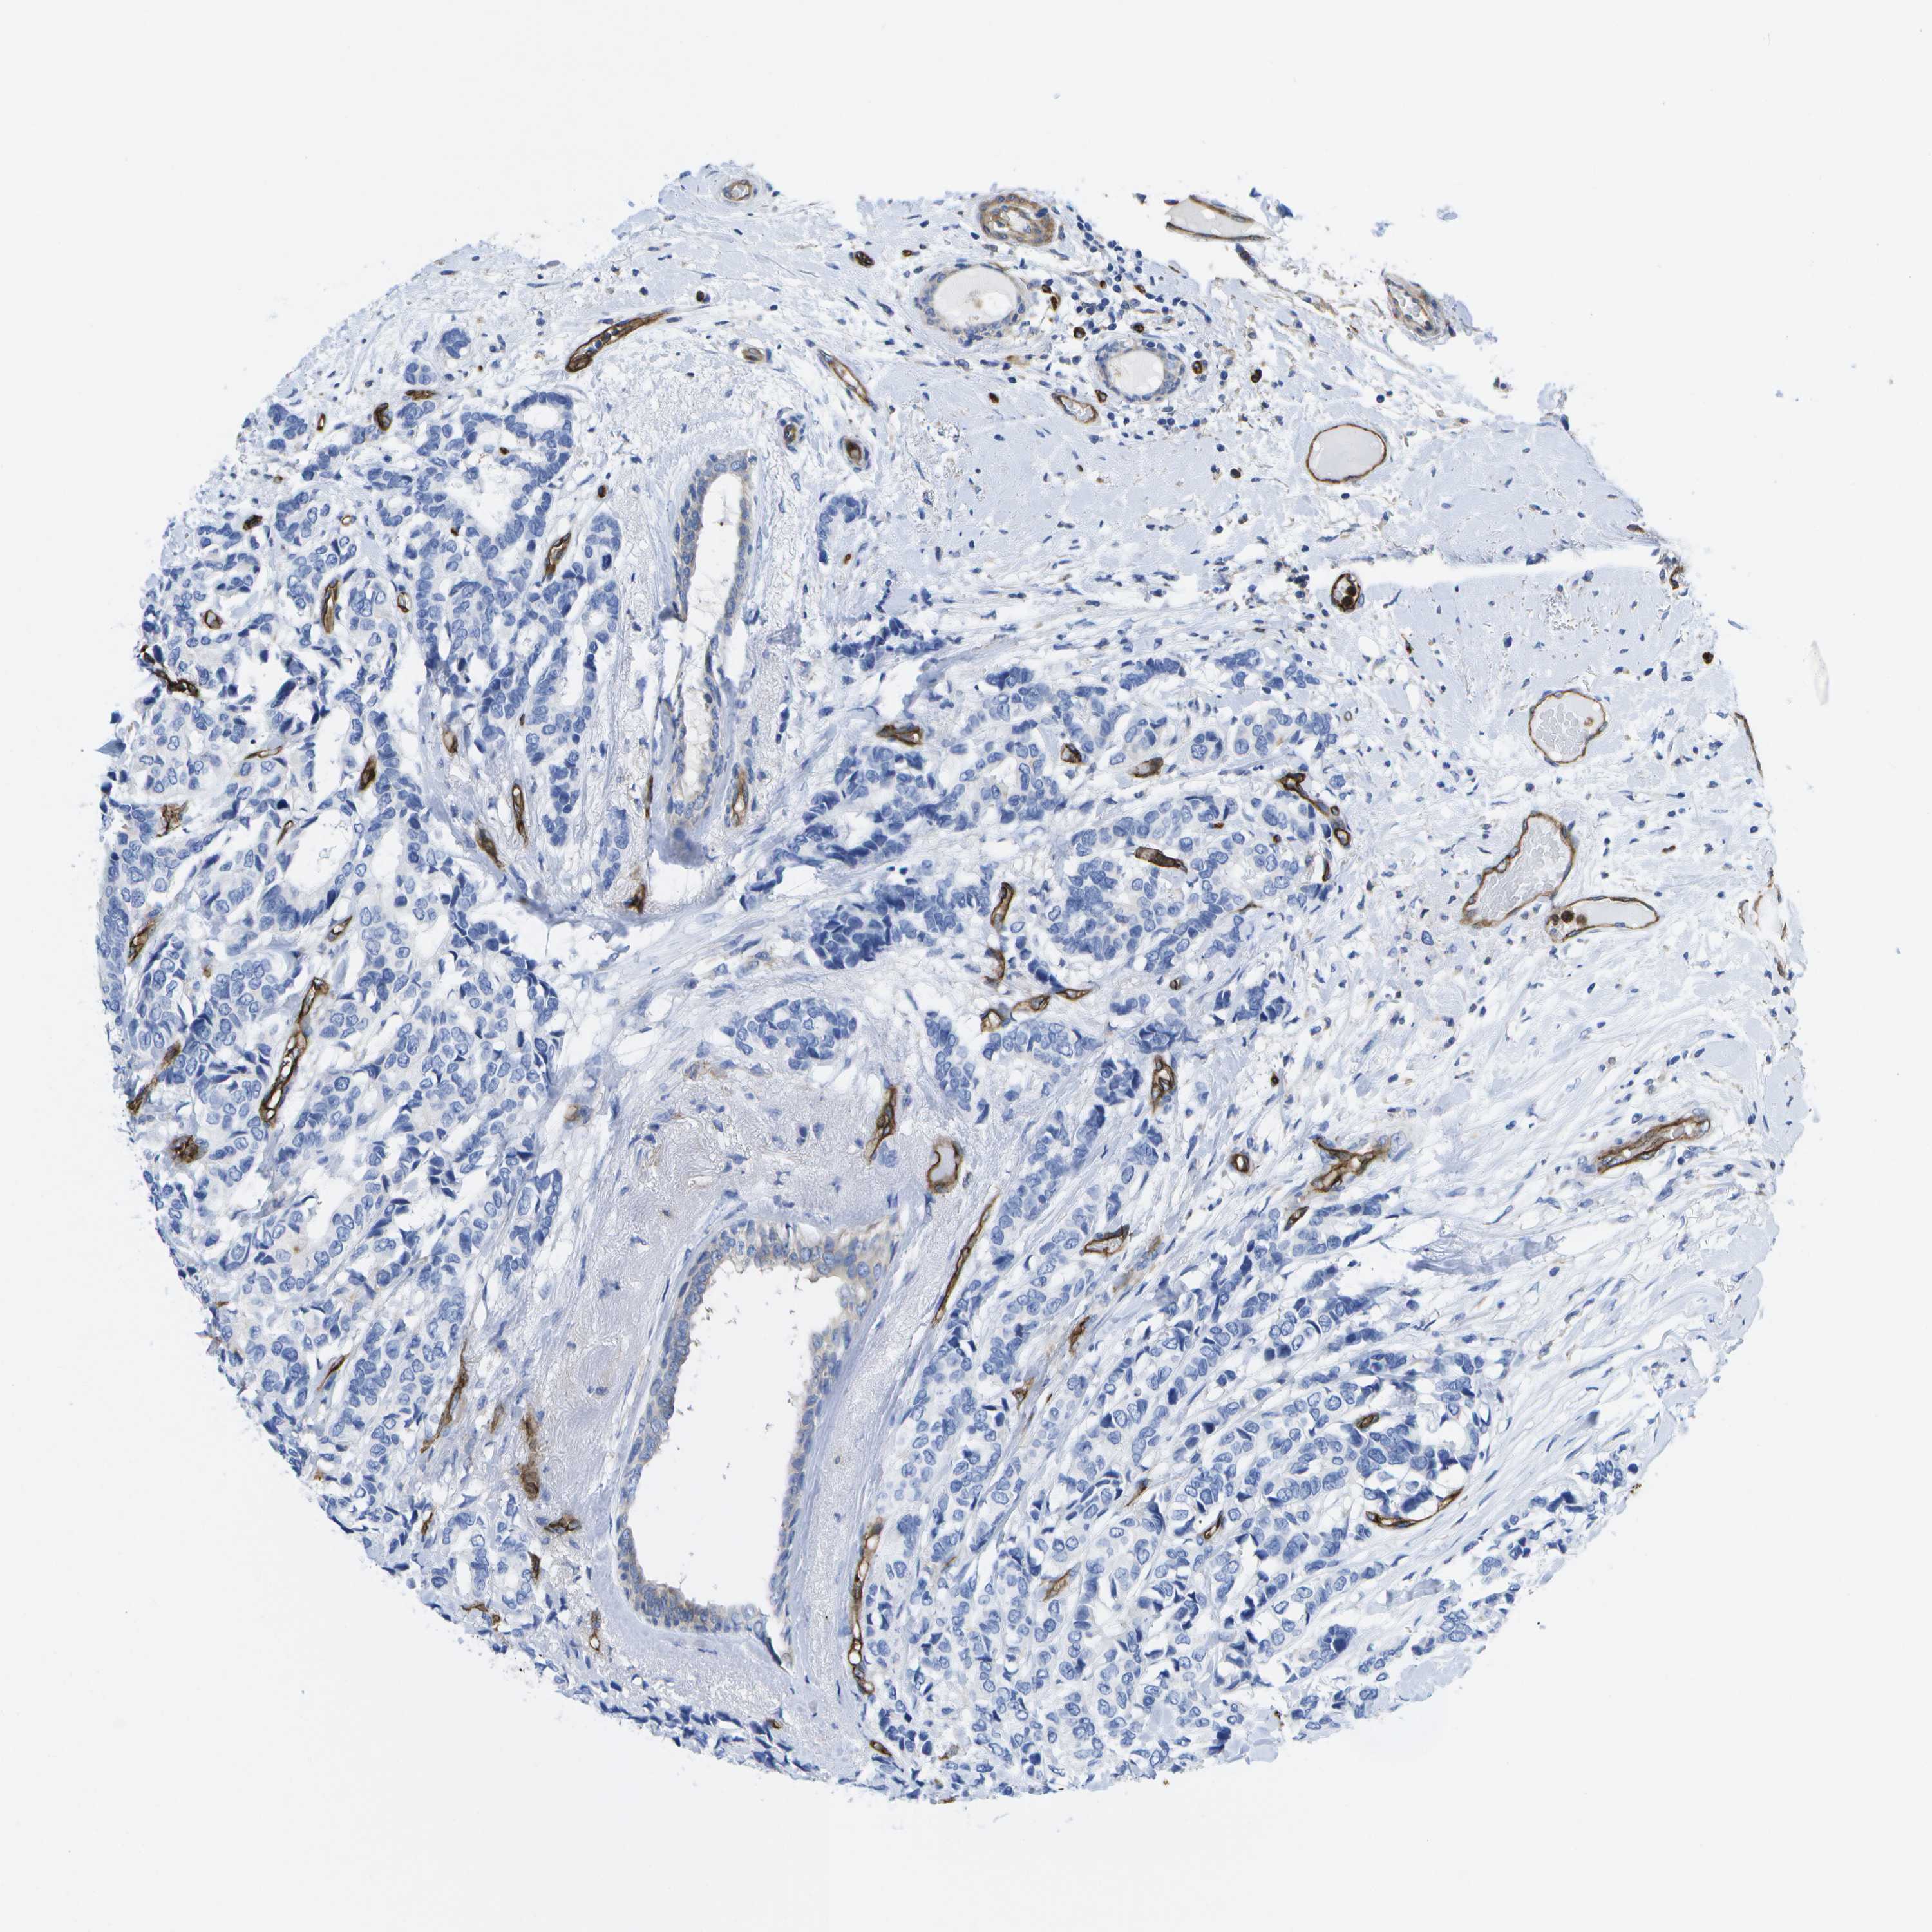

CANCER BREAST CANCER Show tissue menu

BRCA TCGA BRCA VALIDATION PROTEIN EXPRESSION